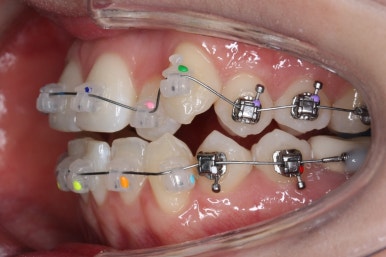

부산부정교합 키다리아저씨치과에 처음 내원하셨을 때의 입안 모습입니다.

위아래 앞니가 삐뚤고 특히 왼쪽 위 송곳니는 밖으로 두드러져 덧니 양상입니다. 윗니는 덧니쪽으로 쏠려 있어서 치열의 중앙이 맞지 않습니다.

전반적인 삐뚤어진 양, 돌출의 느낌, 골격의 비율 등을 고려했을 때 발치 없이 치료를 하기로 했습니다.